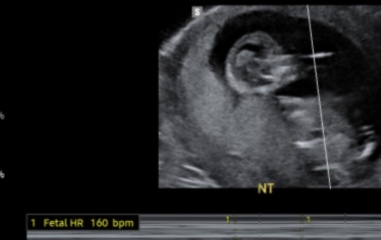

Hello, I have just had my 12 scan and super excited to find out if it’s a boy or a girl but will wait until my 20 scan! Busy analysing all the old wives tales 😂 Any guesses would be greatly appreciated. This is my third baby due January 2024!

12 week scan - nub/ skull theory

Congratulations. Skull theory has been disproven, but nub theory can be very accurate. I’d say yours looks girly

Looks parallel to the spine at the moment so I would say girl but if you’re less than 12+6 gestation there’s still time for a rise!

12+4 days on this scan.

I am 15 weeks + now. Got my gender scan on the 10th August.

what do guys think? Girl or boy, using the nub/skull theory?